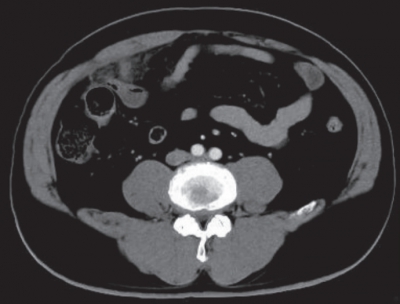

血液所見:赤血球 486 万、Hb 15.0 g/dL、Ht 44 %、白血球 18,000(好中球82 %、好酸球 1 %、好塩基球 1 %、単球 6 %、リンパ球 10 %)、血小板 26 万、PTINR 0.9(基準 0.9~1.1)。 血液生化学所見: 総蛋白 8.1 g/dL、 アルブミン5.1 g/dL、総ビリルビン 1.2 mg/dL、AST 23 U/L、ALT 30 U/L、LD 166 U/L(基準 120~245)、ALP 39 U/L(基準 38~113)、γ-GT 25 U/L(基準 8 ~50)、アミラーゼ 44 U/L(基準 37~160)、CK 64 U/L(基準 30~140)、尿素窒素 17 mg/dL、クレアチニン 1.2mg/dL、 尿酸 6.4 mg/dL、 血糖 109 mg/dL、Na 140 mEq/L、K 3.9 mEq/L、Cl 101 mEq/L、Ca 9.8 mg/dL。CRP 19 mg/dL。 腹部造影 CTを別に示す。

この患者の治療法で適切なのはどれか。

a. 緊急手術